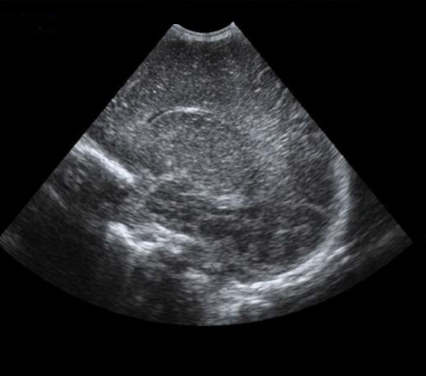

Neonatology Homogeneous Brain 1 Image